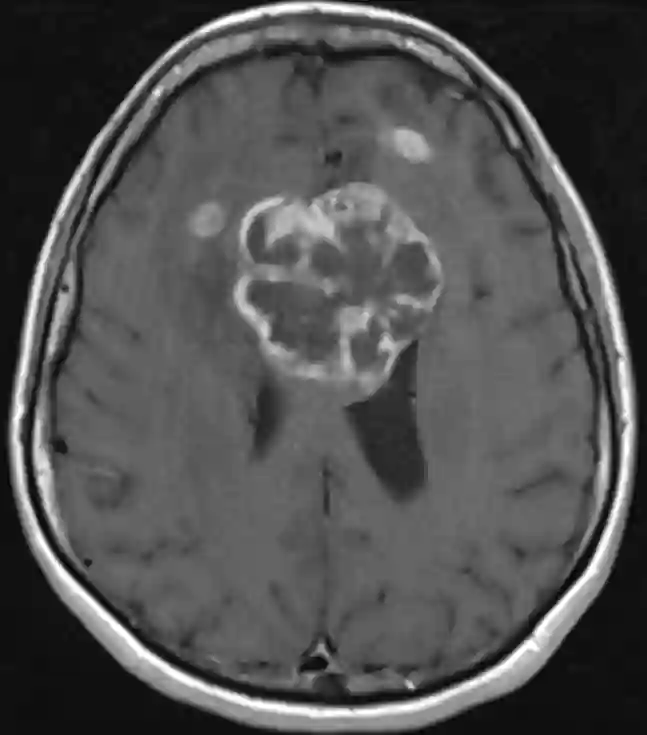

Unter einem Butterflygliom oder auch Schmetterlingsgliom versteht man ein Gliom, welches sich auf die kontralaterale Hemisphäre ausbreitet, zum Beispiel durch den Balken. Eine Studie konnte bei Schmetterlingsglioblastomen zeigen, dass sich die Lebensqualität gemessen am KPS nicht signifikant ändert bei einer chirurgischen Dekompression im Vergleich zu einer Biopsie bei einer insgesamt sehr limitierten Lebensprognose.